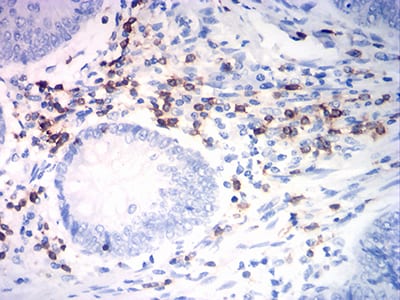

分类: 科研抗体货号: 31807别名: K20; CD20; CK20; CK-20; KRT21应用: IHC反应种属: Human